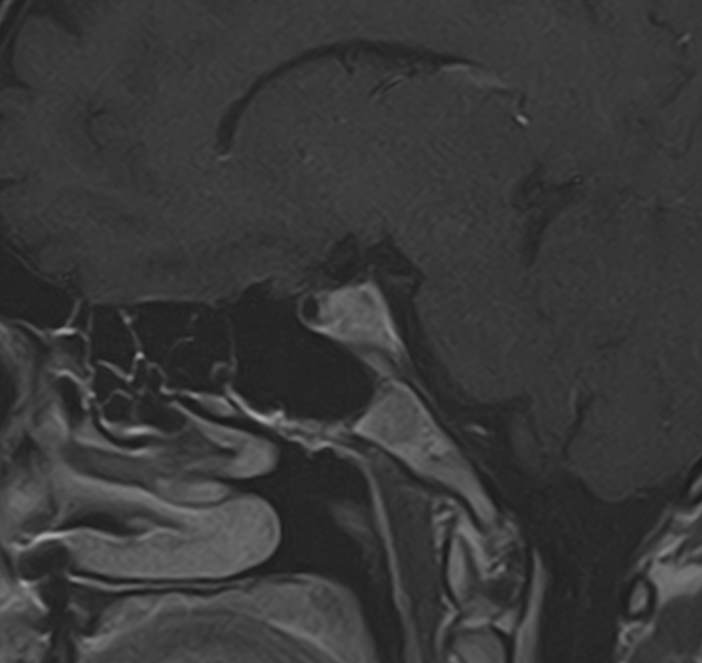

Для выявления опухолевых образований гипофиза проводится МРТ гипофиза с контрастным усилением. Для этого пациенту внутривенно вводится препарат, содержащий контрастное вещество, имеющее в своем составе металл гадолиний. Контрастное вещество избирательно накапливается в патологических очагах, интенсивность этого накопления можно оценить визуально, а также с помощью компьютерной программы — в цифровом выражении.

Метод позволяет создавать детализированные изображения области турецкого седла и является лучшим способом диагностики любых объемных образований гипофиза. С помощью МРТ гипофиза можно выявить макроаденомы и большинство микроаденом гипофиза размером от 1 мм.

В клинике «Доступная медицина» проводится МРТ гипофиза с контрастом на современном высокопольном томографе TOSHIBA VANTAGE TITAN 1,5 Тесла. Индукция магнитного поля 1,5 Тесла обеспечивает высокую четкость изображения и отвечает мировым стандартам качества диагностики заболеваний центральной нервной системы.